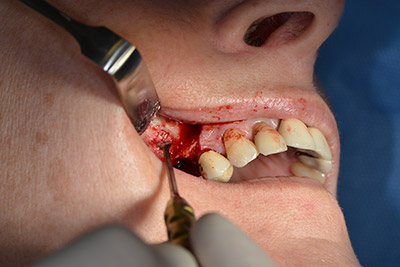

Sky implants (bredent) were used this case. The surgical protocol of these, specify pilot drilling at about 1200 rpm (Fig. 9).

The following holes were drilled at a reduced speed of 300 rpm. The Implantmed demonstrated its true capability at this stage. The surgical protocol can be preset – the various positions can be selected simply by pressing the “P” position of the foot control (Fig. 10 to 11).